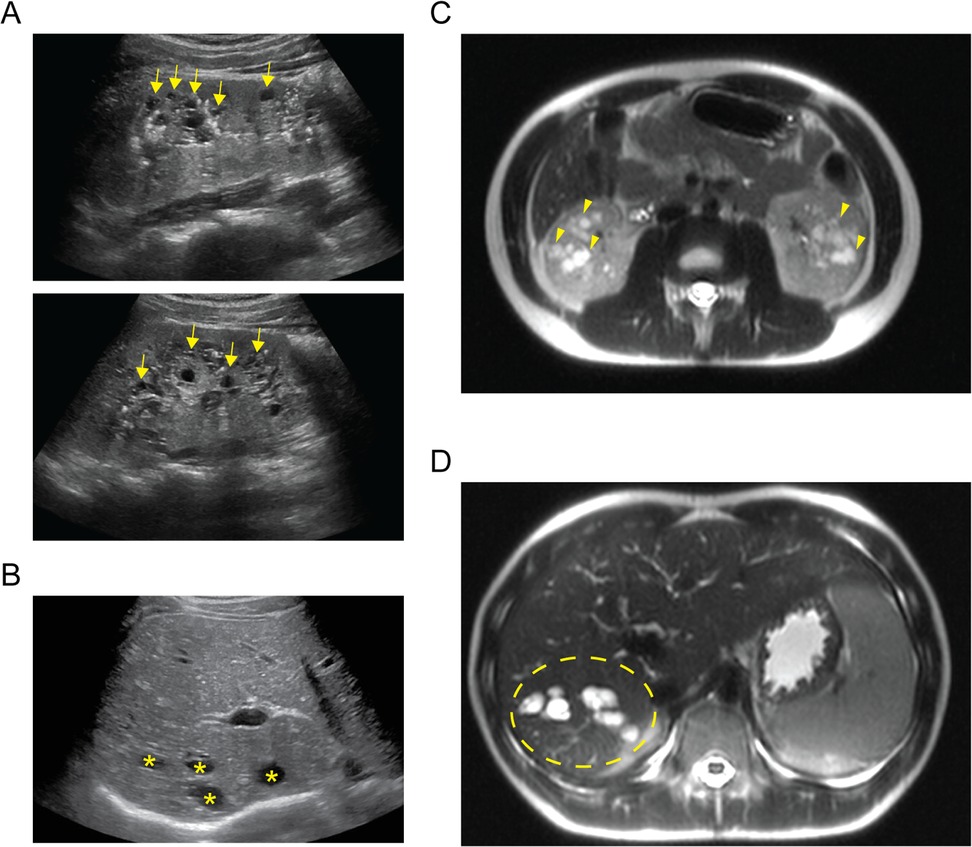

A 14-year-old XY boy initially presented to the nephrology clinic following an abdominal ultrasound that found multiple cortical kidney cysts and multiple hepatic cysts (Figures 1A,B). On initial laboratory evaluation, he was found to have abnormalities consistent with chronic kidney disease (CKD). He had a serum creatinine level of 1.15 mg/dL, albumin of 4.7 g/dL, blood urea nitrogen of 26 mg/dL, potassium of 4.3 mmol/L, bicarbonate of 21 mmol/L, calcium of 9.9 mmol/L, and 1+ protein in his urine. He underwent magnetic resonance imaging (MRI) of the abdomen to further delineate the cystic structures (Figures 1C,D). His liver and kidney cysts had a maximal volume of 14,137 and 179 mm3, respectively. His history was significant with a previously identified small unspecified number of hepatic cysts found incidentally during ultrasound evaluation in the setting of a prior gastrointestinal illness at 8 months of age. His kidneys were not cystic during the prior imaging, and he had no dietary history that would contribute to decreased kidney function. Similarly, he had no history of severe or frequent infections that would increase his risk for decreased kidney function. He was not taking any routine medication and had no history of exposure to known nephrotoxic agents.

Figure 1. Imaging of cystic organ changes. (A) Sagittal ultrasound images of right (upper) and left (lower) kidneys demonstrating diffuse cystic changes predominantly affecting the medullary parenchyma (examples indicated with yellow arrows). (B) Transverse ultrasound image of the liver demonstrating cystic spaces of varying size affecting the hepatic parenchyma (examples indicated with yellow asterisks). (C) Axial T2-weighted MRI cross section demonstrating extensive kidney cystic changes bilaterally (examples indicated with yellow arrowheads). (D) Axial T2-weighted MRI cross section demonstrating extensive cystic changes within the right hepatic lobe (affected area within area demarcated by yellow dashed ellipse).